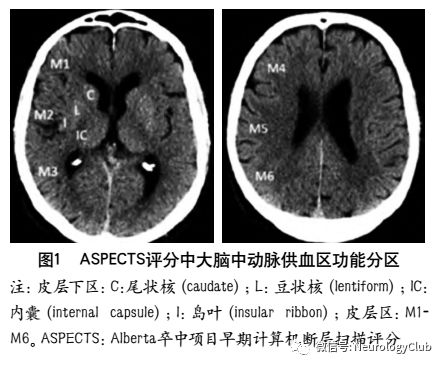

3.2.1 ASPECTS评分

ASPECTS评分是基于NCCT评估MCA区域早期缺血改变简单而系统的一种方法。将MCA供血区各主要功能区分别赋分(4个皮层下区:尾状核C、豆状核L、内囊IC、岛叶I;6个皮层区,标志为M1-M6)(图1),共计10分,每累及一个区域减去1分,即正常脑CT为10分,MCA供血区广泛梗死则为0分

为评估后循环梗死患者早期梗死情况,PUETZ等建立了评估后循环的AIS预后早期CT评分(posterior circulation Acute Stroke Prognosis Early CT score,pc-ASPECTS)。pc-ASPECTS总分也是10分:双侧丘脑和小脑各1分,双侧大脑后动脉供血区各1分,中脑和脑桥为2分(图2)